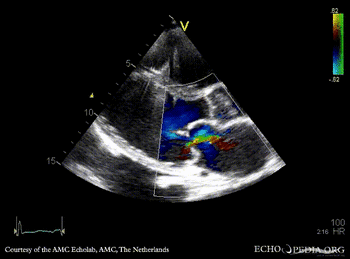

Severe prolaps of PMVL

PSAX: flattening of IAS, enlarged right ventricle PSAX: prolaps of PMVL